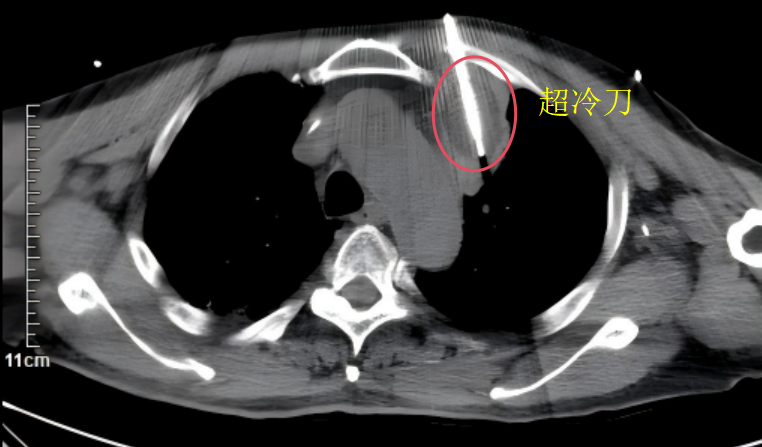

此次手术由胸外科副主任邹耀罡主任医师主刀,陈敏副主任医师与护士长杨丽华副主任护师组成的专业团队协同开展。术中,团队凭借丰富的临床经验和精准的操作技巧,在CT实时影像引导下,将直径约2mm的康博刀消融针精准置入肿瘤靶区,通过两个循环的“深度冷冻-主动复温”治疗——先将病灶温度降至-196℃的超低温,再快速升温至85℃,形成的“冰球”完整覆盖整个肿瘤病灶,实现对肿瘤组织不可逆的精准损毁。整场手术耗时短、创伤小,患者术中生命体征平稳,顺利完成,无并发症出现。术后,患者恢复良好,生活质量明显提升,一家人对治疗效果十分满意。